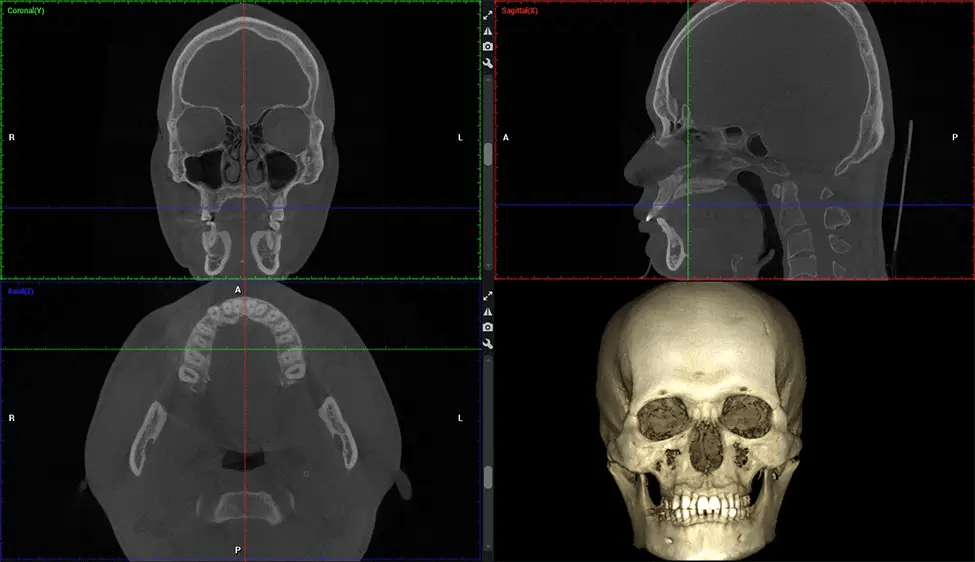

Cone Beam Computed Tomography (CBCT) is an advanced imaging technique used in dentistry and maxillofacial surgery to obtain detailed 3D images of the oral and maxillofacial structures. At Dr G Dental Studio, our CBCT scanners utilize a cone-shaped X-ray beam and a specialized detector to capture images from different angles. A computer then combines these images to create a 3D representation of the patient’s oral anatomy.

This 3D scan, called cone beam computed tomography, gives your dentist a more complete image of your oral anatomy and disease processes than a traditional X-ray. Unlike conventional X-rays, which capture a 2D image of your mouth from various angles, a 3D scan takes multiple digital X-rays for one image. It provides a complete view of your jaw, teeth, nerves, and soft tissues. This enhanced view allows dentists to detect minor issues not visible in traditional 2D scans, such as impacted wisdom teeth or bone fractures in the sinus cavity.

There are many benefits to using CBCT technology, especially compared to the traditional 2D X-ray format. One of the most significant advantages of CBCT scans is that they provide much more information than traditional X-rays. A scan lets your dentist see images from all angles of your jaw and mouth, including your sinuses, nasal cavity, cheekbones, and other surrounding areas. This added information helps your dentist craft a comprehensive treatment plan that addresses all aspects of your oral health.

After the scanning process, the captured X-ray images are processed by the CBCT software, which applies algorithms to reconstruct a detailed 3D image of the scanned area. The software compiles these individual X-ray images and creates a digital 3D representation of the patient’s anatomy. The reconstructed 3D CBCT image can be viewed and analyzed by the dentist or radiologist. This image can be manipulated, rotated, and zoomed in or out to examine specific structures and evaluate the patient’s condition.